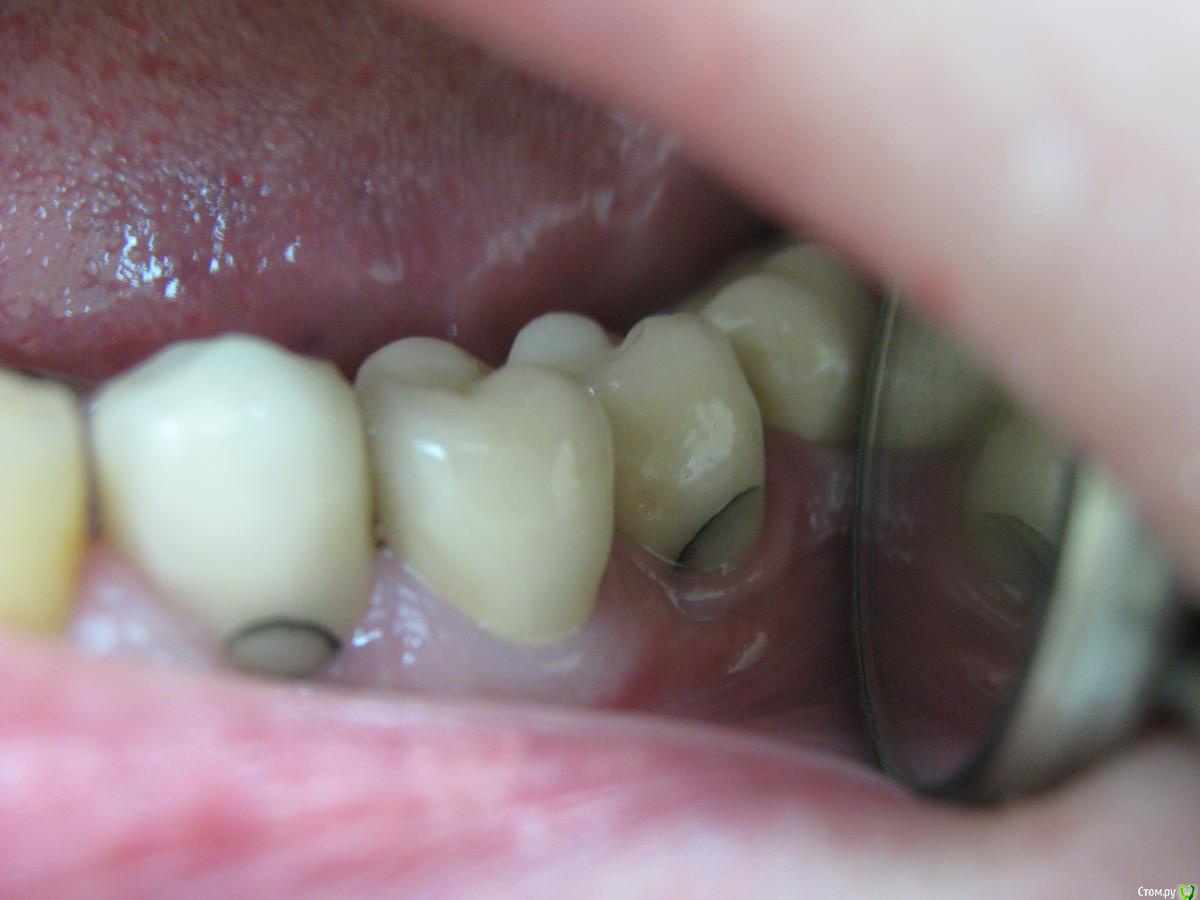

Кирилл 1986 Опубликовано 15 февраля, 2017 Поделиться Опубликовано 15 февраля, 2017 Уважаемые коллеги, какие могут быть причины появления подобных трещин?3.4,3.6 - коронки на имплантатах (цементная фиксация), 3.5 - коронка на зубе. Фиксированы 1.5 года назад.Потемнения появились только сейчас. Ранее никаких жалоб не было. Раз в полгода пациенту проводились чистки. Ссылка на комментарий

zubovolok Опубликовано 16 февраля, 2017 Поделиться Опубликовано 16 февраля, 2017 Уважаемые коллеги, какие могут быть причины появления подобных трещин?3.4,3.6 - коронки на имплантатах (цементная фиксация), 3.5 - коронка на зубе. Фиксированы 1.5 года назад.Потемнения появились только сейчас. Ранее никаких жалоб не было. Раз в полгода пациенту проводились чистки.присоединяюсь к вопросу, точно такие же "полосы" появляются на мк коронках на цементной фиксации на абатментах, не зондируются,а росполагаются как будто внутри. В нашей клинике не у одного меня такая проблема и техники разные. Грешили на металл, поменяли, все равно появляются. Достаточно работ уже переделал. Не знаем что делать, коллеги подскажите?! Ссылка на комментарий